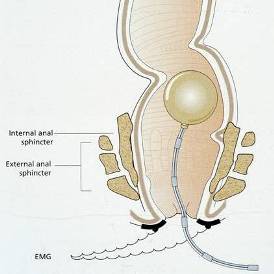

Sakrale Nervenstimulation

Eine neue, vielversprechende Therapie, die wir in enger Zusammenarbeit mit den Chirurgen anbieten, ist die sakrale Nervenstimulation (sakrale Nervenmodulation).

Bei der sakralen Nervenstimulation (SNS) wird mittels Elektroden Strom an die Sakralnerven gebracht, wodurch die Beckenbodennerven stimuliert werden, die ihrerseits die Muskelaktivität des Beckenbodens und damit auch die Schliessmuskelfunktion verbessern. Diese minimal-invasive Methode kommt zum Einsatz, wenn der Stuhlinkontinenz kein anatomischer Defekt zugrunde liegt.